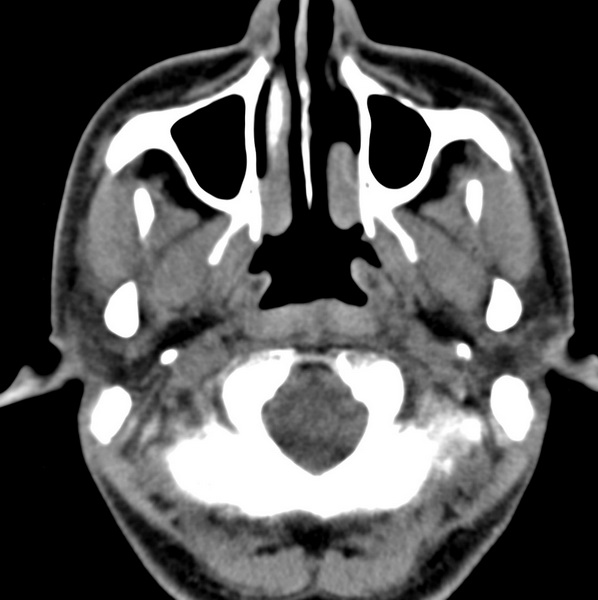

男、31、鼻咽部肿瘤放疗后请帮忙看看。

效果好,右侧破裂孔扩大,局部骨质缺损,为颅底骨质破坏。

1)鼻咽部肿瘤侵犯颅底放疗术后改变。2)左侧蝶窦炎。

咽后壁增厚,左侧咽鼓管隆突增大、咽鼓管咽口变浅,同侧咽旁间隙较窄。右侧颅底骨质破坏?为什么不在同一侧?

鼻咽部肿瘤侵犯颅底放疗术后改变.